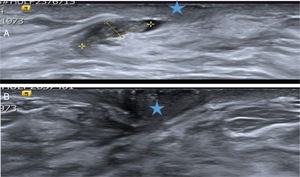

A. Papiloma atípico. Paciente de 40 años con secreción uniorificial de mama derecha. La ecografía mostró un probable PB (señalado por las cruces amarillas) dentro del ducto secretor dilatado, cercano al pezón (estrella azul). Hallazgo BIRADS 3. Se extirpó con BAV y el diagnóstico histológico fue de PA. B. Ecografía de control a los 26 meses. Se objetivó el área de la biopsia previa cercana al pezón (estrella azul), sin signos de lesión recidivante. Los cambios cicatriciales de la BAV previa no eran visibles. La secreción desapareció después de la BAV.